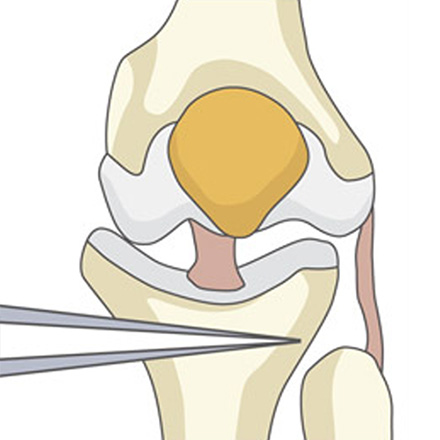

02

정강이뼈 윗부분을 미세하게 벌려 인공뼈를 넣을 공간을 만들어줍니다.